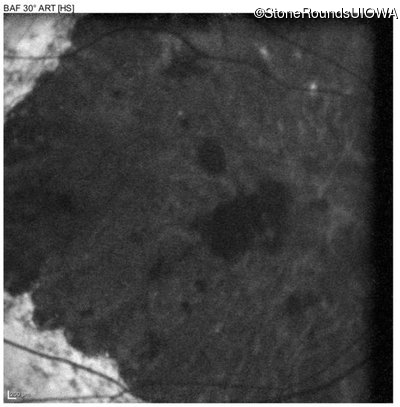

Blue Autofluorescence - Left - 20/300 sc

Exemplar